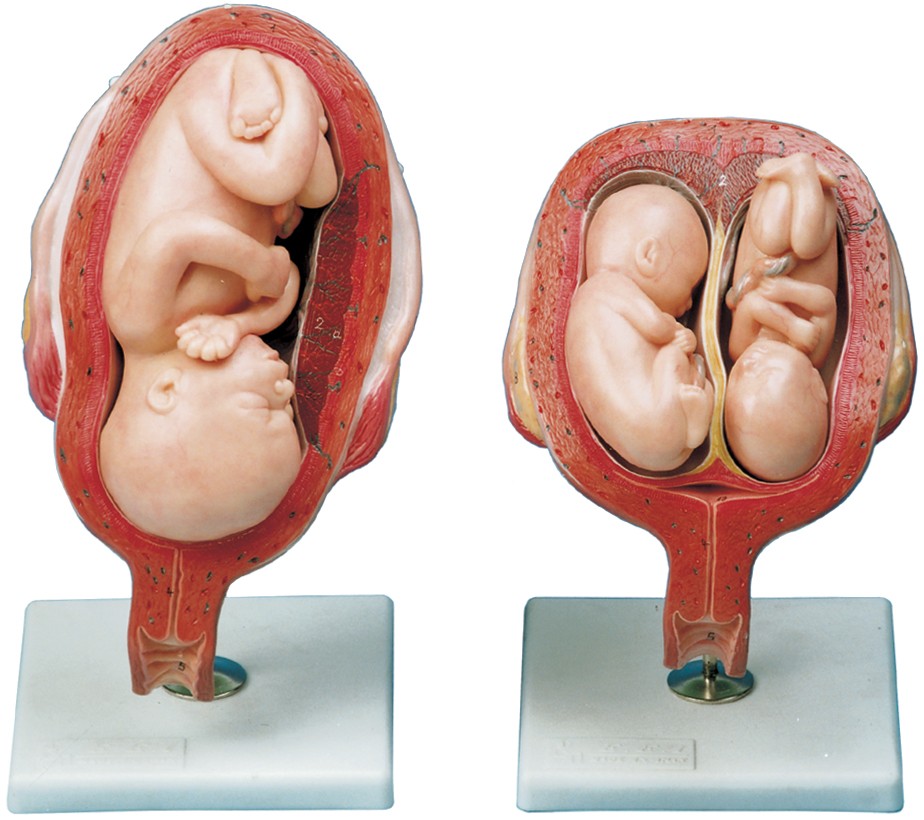

مولاژ کلمه ای فرانسوی به معنای قالب است. آناتومی بدن انسان با تجهیزاتی مانند مولاژهای پزشکی یا کالبدشناسی که نمونه هایی تخصصی و شبیه به اندام های بدن انسان هستند، به دانش آموزان و دانشجویان آموزش داده می شود. استفاده از مولاژ در روند یادگیری و آموزش تاثیر به سزایی داشته و تمامی اندام ها را با تمامی جزئیات و با کیفیت بالا می توان مشاهده و بررسی کرد. مولاژها عموما از جنس PVC نشکن، لاستیک یا فوم ساخته شده و دارای رنگ طبیعی و قابل شست و شو هستند. برخی از انواع مولاژها مناسب برای آموزش مراقبت های پزشکی و پرستاری است و امکان تمرین بانداژ، تزریق، CPR، جراحی و... وجود دارد. مولاژها معمولا هر کدام عضوی از بدن را نمایش می دهند و قابلیت تفکیک و مشاهده همه بخش های آن وجود دارد.

مولاژها معمولا با توجه به نوع اعضا و یا دستگاه های بدن در اندازه طبیعی، کوچکتر و یا چندین برابر بزرگتر ساخته می شوند تا امکان مشاهده دقیق اجزای آن ها فراهم شود. برخی مولاژها از چندین قطعه ساخته شده اند که قابلیت تفکیک دارند. علاوه بر نمایش ساختار و نحوه عملکرد اعضای بدن، ماهیچه ها و عضلات بدن را نیز می توان به کمک مولاژها مشاهده کرد.

مولاژها ابزاری تخصصی برای آموزش دانشجویان پزشکی، دندان پزشکی، پرستاری و مامایی است. همچنین در مدارس و سایر مراکز آموزشی میتوان از انواع مولاژها برای بهبود یادگیری و آموزش بهره برد. در کلینیک های زنان و زایمان، دندان پزشکی، سالن های تشریح، بیمارستان ها و آزمایشگاه ها نیز مولاژهای مراحل حاملگی، انواع دندان و بیماری های آن کاربرد دارند.